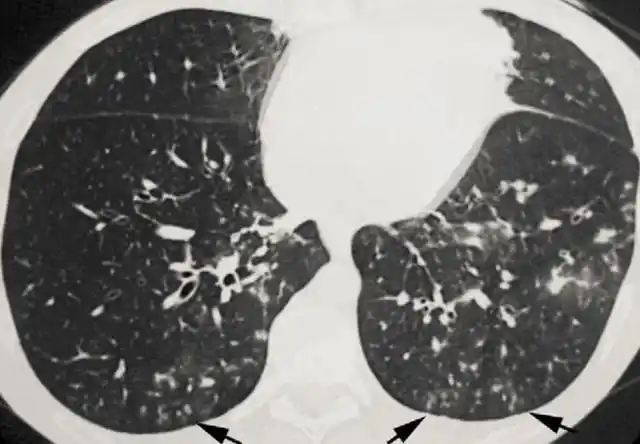

肺炎的影像诊断和鉴别诊断